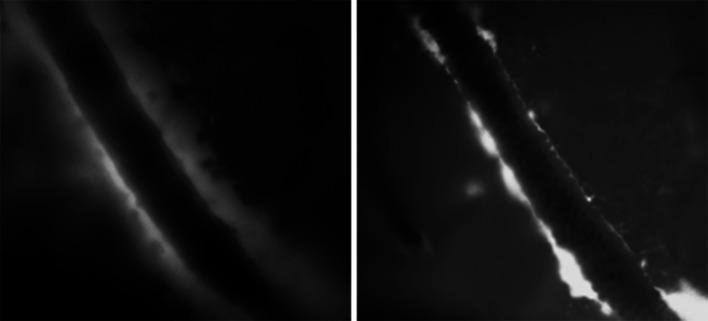

The lymphatic clearance pathways of the brain are different compared to the other organs of the body and have been the subject of heated debates. Drainage of brain extracellular fluids, particularly interstitial fluid (ISF) and cerebrospinal fluid (CSF), is not only important for volume regulation, but also for removal of waste products such as amyloid beta (Aβ). CSF plays a special role in clinical medicine, as it is available for analysis of biomarkers for Alzheimer's disease. Despite the lack of a complete anatomical and physiological picture of the communications between the subarachnoid space (SAS) and the brain parenchyma, it is often assumed that Aβ is cleared from the cerebral ISF into the CSF. Recent work suggests that clearance of the brain mainly occurs during sleep, with a specific role for peri- and para-vascular spaces as drainage pathways from the brain parenchyma. However, the direction of flow, the anatomical structures involved and the driving forces remain elusive, with partially conflicting data in literature. The presence of Aβ in the glia limitans in Alzheimer's disease suggests a direct communication of ISF with CSF. Nonetheless, there is also the well-described pathology of cerebral amyloid angiopathy associated with the failure of perivascular drainage of Aβ. Herein, we review the role of the vasculature and the impact of vascular pathology on the peri- and para-vascular clearance pathways of the brain. The different views on the possible routes for ISF drainage of the brain are discussed in the context of pathological significance.

与身体的其他器官相比,大脑的淋巴清除途径有所不同,一直是激烈争论的主题。脑内细胞外液的引流,特别是间质液(ISF)和脑脊液(CSF),不仅对容量调节很重要,而且对清除淀粉样β蛋白(Aβ)等废物也很重要。脑脊液在临床医学中起着特殊作用,因为它可用于分析阿尔茨海默病的生物标志物。尽管蛛网膜下腔(SAS)与脑实质之间的通讯缺乏完整的解剖学和生理学图景,但人们通常认为Aβ从脑内间质液清除进入脑脊液。最近的研究表明,大脑的清除主要发生在睡眠期间,血管周围和血管旁间隙作为脑实质的引流途径发挥着特定作用。然而,流动方向、涉及的解剖结构和驱动力仍然不明确,文献中的数据部分相互矛盾。阿尔茨海默病中神经胶质界膜中Aβ的存在表明间质液与脑脊液直接相通。尽管如此,也有关于与Aβ血管周围引流失败相关的脑淀粉样血管病的详细描述的病理学。在此,我们综述了脉管系统的作用以及血管病理学对大脑血管周围和血管旁清除途径的影响。在病理意义的背景下讨论了关于脑内间质液引流可能途径的不同观点。